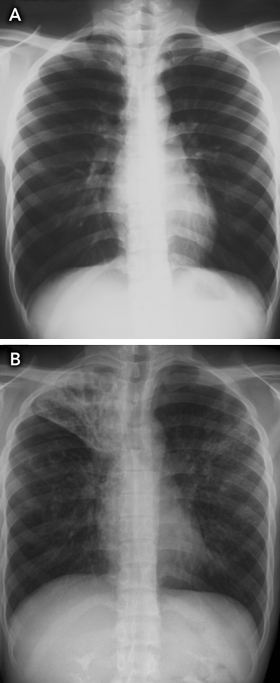

As the median time between arrival in Australia and notification of TB was 2 years (indicating that some patients may have arrived with active TB), another strategy that might improve TB control is pre-departure screening for active TB, particularly in resource-limited settings. For example, the Australian Government Department of Immigration and Citizenship could develop guidelines for countries performing pre-migrant screening that outline minimum laboratory standards for TB culture testing for applicants with abnormal chest x-ray findings. Unfortunately, this strategy would still not detect most people entering Australia who have latent TB and normal chest x-ray findings when they obtain their visa (Box 6).

Results: From 1998 to 2007, 31 patients who resided in Victoria were diagnosed with MDR-TB. The median age of patients was 27 years, most patients were born overseas, and more than half were full-time students. The median time between arrival in Australia and notification of TB was 2 years, and 24 patients were notified to the Department within 5 years of arrival. Twenty patients had pulmonary disease; in 12 of these patients, sputum was smear-positive for acid-fast bacilli. The median treatment period for patients who completed treatment was 22 months.